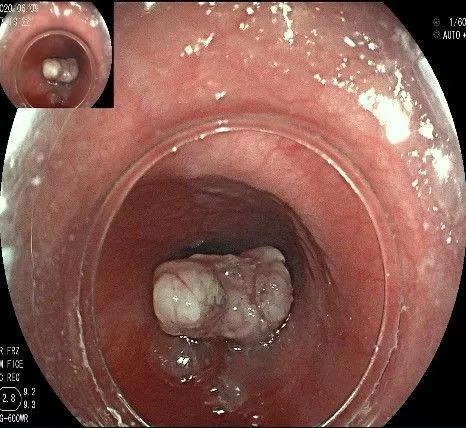

此时瘤体基底部已暴露出来,起源于固有肌层。

这是最后的“根”部。

换用IT刀可以轻松剥离,又避免切入过深造成穿孔。

剥离接近完成,最后连接的薄层组织。